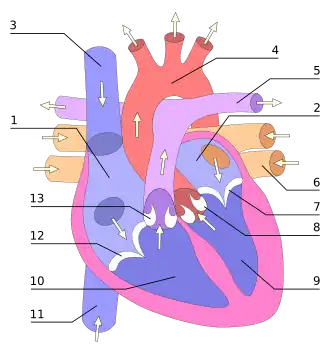

Сердце птиц и млекопитающих (зверей) — четырёхкамерное. Различают: правое предсердие, правый желудочек, левое предсердие и левый желудочек. Кровообращение: из одной или двух передних (верхних) и задней (нижней) полых вен кровь поступает в правое предсердие, затем в правый желудочек, затем по малому кругу кровообращения кровь проходит через лёгкие, где обогащается кислородом (оксигенируется), поступает в левое предсердие, затем в левый желудочек и, далее, в основную артерию организма — аорту (птицы имеют правую дугу аорты, млекопитающие — левую). Большой и малый круги кровообращения полностью разобщены.

Между предсердиями и желудочками находятся фиброзно-мышечные клапаны — справа трёхстворчатый (или трикуспидальный), слева двустворчатый (или митральный). На выходе из желудочков соединительнотканные клапаны (лёгочный справа и аортальный слева). Клапаны открываются только в сторону желудочков и поэтому пропускают кровь только в одном направлении: из предсердий в желудочки. Открываться в сторону предсердий створкам клапанов мешают сухожильные нити, отходящие от поверхности и краёв клапанов и прикрепляющиеся к мышечным выступам желудочков. Мышечные выступы, сокращаясь вместе с желудочками, натягивают сухожильные нити, чем препятствуют выворачиванию створок клапанов в сторону предсердий и обратному оттоку крови в предсердия.

Предсердия открываются в желудочки через атриовентрикулярные клапаны, присутствующие в межжелудочковой перегородке. Это различие видно также на поверхности сердца, как коронарная борозда. В верхнем правом предсердии имеется структура в виде уха, называемая придатком правого предсердия, или ушной раковиной, и ещё одна в верхнем левом предсердии — придаток левого предсердия. Правое предсердие и правый желудочек вместе иногда называют правым сердцем. Точно так же левое предсердие и левый желудочек называют левым сердцем. Желудочки отделены друг от друга межжелудочковой перегородкой, видимой на поверхности сердца в виде передней продольной борозды и задней межжелудочковой борозды.

Сердце человека состоит из четырёх камер, разделённых перегородками и клапанами. Кровь из верхней и нижней полой вены поступает в правое предсердие, проходит через трикуспидальный клапан (он состоит из трёх лепестков) в правый желудочек. Затем через лёгочный клапан и лёгочный ствол поступает в лёгочные артерии, идёт к лёгким, где происходит газообмен и возвращается к левому предсердию. Затем через митральный (двухстворчатый) клапан поступает в левый желудочек, затем проходит через аортальный клапан в аорту.

В правое предсердие входят полые, в левое предсердие — лёгочные вены. Из правого и левого желудочка выходят, соответственно, лёгочная артерия (лёгочный ствол) и восходящая аорта. Правый желудочек и левое предсердие замыкают малый круг кровообращения, левый желудочек и правое предсердие — большой круг. Сердце входит в состав органов среднего средостения, бо́льшая часть его передней поверхности прикрыта лёгкими. Со впадающими участками полых и лёгочных вен, а также выходящими аортой и лёгочным стволом оно покрыто сорочкой (сердечной сумкой или перикардом). В полости перикарда содержится небольшое количество серозной жидкости. У взрослого человека его объём и масса составляют в среднем для мужчин 783 см3 и 332 г, для женщин — 560 см3 и 253 г.